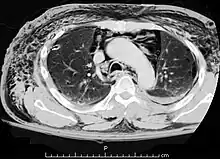

![]() | |

| A CT scan showing air in the mediastinum | |